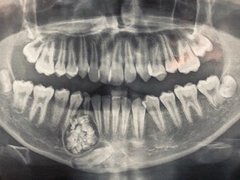

Hi hữu: Lấy gần 100 cái răng trong miệng một thiếu niên ở Khánh Hòa

Bệnh viện Đa khoa tỉnh Khánh Hòa cho biết vừa thực hiện ca phẫu thuật hi hữu lấy gần 100 cái răng của một bệnh nhân